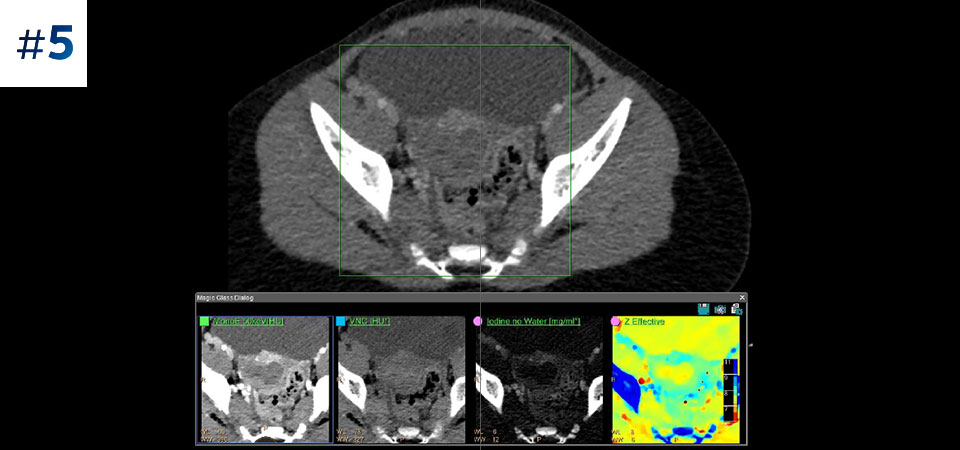

Ograniczenie liczby ponownych badań Udoskonalona charakterystyka i wizualizacja tkanek może ograniczyć konieczność wykonywania ponownych badań, jaka zachodzi w przypadku badań o niezadowalającej jakości oraz przypadkowych obserwacji.

Opracowany przez firmę Philips tomograf komputerowy z detektorem spektralnym umożliwia akwizycję konwencjonalnych i spektralnych danych

w ramach jednego badania — bez konieczności zmiany stosowanych procedur pracy.

Zobacz jak tomograf spektralny pomaga w diagnostyce pacjentów onkologicznych.